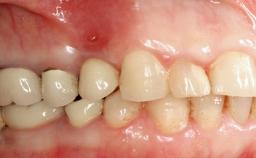

A 27-year-old male was referred to the periodontist for assessment and management of implant site 41. The implant had been placed nine years previously and restored with a screw-retained single crown. The patient was a cigarette smoker in good general health. He reported he had reduced his smoking habit from 25 cigarettes per day to 15 cigarettes per day in the previous six months. On examination, there was calculus and plaque present at the lower anterior teeth and at implant site 41. Localized attachment loss was observed at teeth 32 and 42, with 2–3 mm of gingival recession. At implant site 41, there were 8–9 mm probing depths with suppuration and bleeding on probing.